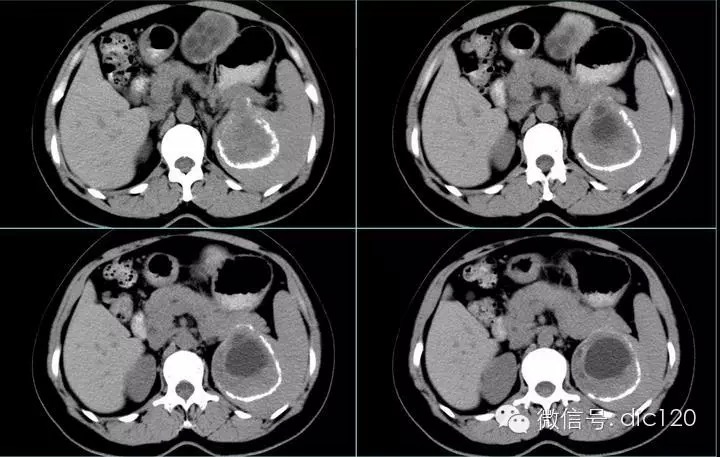

肝脏、脾脏、腹腔包虫病一例

简要病史:患者于入院前19年因诊“卵巢囊肿”行手术治疗,术中诊断为包虫病,术中囊液污染腹腔。术后患者恢复良好。患者于3年前无意中发现左上腹部出现一包块,约3*3cm大小,无触痛,活动度可,无发热、乏力,无恶心、呕吐,无腹痛、腹泻,无胸闷、气短,无皮疹等不适,查B超考虑肝包虫(多发)、脾肾间隙处实性占位,考虑包虫。

(3)囊壁可见钙化,呈壳状或环状,厚薄可以规则,为肝包虫病特征性表现。

(4)因感染或损伤,可造成内囊分离,如内、外囊部分分离表现为双边征;如内囊完全分离、塌陷、卷缩,并悬浮于囊叶中,呈水上荷花征。偶尔完全分离脱落的内囊散开呈飘带状阴影。

肝包虫病是牧区较常见的寄生虫,也称肝棘球蚴病。在中国主要流行于畜牧业发达的新疆、青海、宁夏、甘肃、内蒙和西藏等省区。病因犬绦虫寄生在狗的小肠内,随粪便排出的虫卵常粘附在狗、羊的毛上,人吞食被虫卵污染的食物后,即被感染。虫卵经肠内消化液作用,蚴脱壳而出,穿过肠黏膜,进入门静脉系统,大部分被阻留于肝脏内。蚴在体内经3周,便发育为包虫囊。包虫囊肿在肝内逐渐长大,依所在部位引起邻近脏器的压迫症状,并可发生感染,破裂播散及空腔脏器阻塞等并发症。